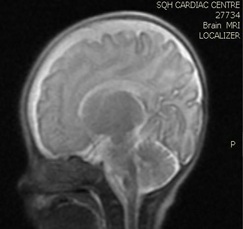

Brain MRI (images 1,2,3,4) at the age of 78 days; revealed that generalized relative simplified gyral pattern, generalized enlarged subarachnoid spaces as well as enlarged bilateral sylvian fissures, no diffusion restriction, no intracerebral hemorrhage, pituitary fossa appears normal in size, the posterior pituitary spot is not well defined.

Image 3

We were able to manage hypernatremia and polyuria with desmopressin and weaned the infant from a high fluid intake to a normal fluid intake per day [10-14]. The desmopressin response validated the diagnosis of central diabetes insipidus. Brain MRI data were also indicative of a central origin, particularly the posterior pituitary spot, which was not well delineated.  In comparison with previously reported cases, we controlled the case with a little dosage of oral desmopressin, and oral desmopressin is more practical than intranasal dDAVP treatment [15,16], and oral desmopressin administration and modification of dosage is easier than nasal application [17].